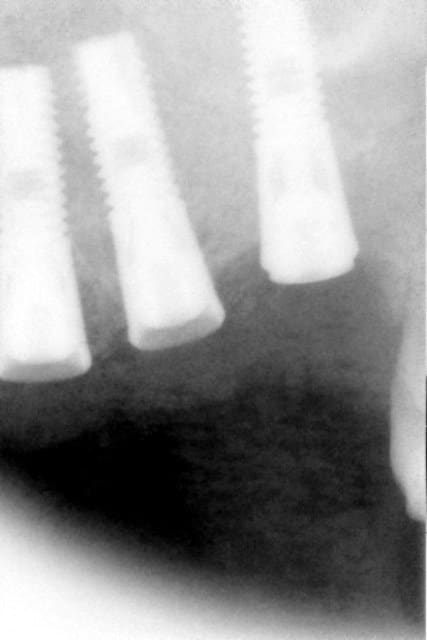

voilà, pour revenir à ce qu'on disait: une petite illustration: 25 et 27 ont été extraites. et voici la suite.

Fenêtre1 f7m7am - Eugenol

Fenêtre 2 qltvye - Eugenol

Pano initiale rhx4jg - Eugenol

Initial rir4cj - Eugenol